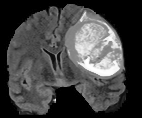

V-C Non-Registered MRI Segmentation Experiments

To demonstrate the robustness of the superpatch structure and the proposed framework, we apply SPM to brain tumor segmentation on multi-modal non-registered Magnetic Resonance Images (MRI). Classical patch-based and multi-atlas structure segmentation methods are based on registered subjects. Consequently, they cannot be efficiently applied in this non-registered context, due to the substantial variation in tumor shape and locations. Superpixels enable to better capture the tumor geometry, thus increasing the segmentation accuracy. Superpixel and supervoxel-based approaches have been applied to tumor segmentation [54]. However, in this work, the neighborhood is not considered and the ANN search is exhaustive, and computed on a large multi-modal histogram descriptor, leading to prohibitive computational time.

SPM can be efficiently applied to tumor segmentation since it quickly finds good correspondences without image registration, and uses the superpixel neighborhood to improve the matching. In this application, the segmentation is computed from a superpixel decomposition [1], then each region (tumor or background) is labeled with SPM.

We present results obtained on the MICCAI multi-modal Brain Tumor Segmentation (BRATS) dataset [49]. This challenging dataset contains real and simulated patient data, with overall poor resolution and large variation of tumor shape and position. For both types, high grade (HG) and low grade (LG) tumors are provided with four modalities: T1, contrast enhanced T1 (T1C), T2, and FLAIR. Overall, there are 20 and 10 real patient data with respectively HG and LG tumors, and 25 images for both HG and LG simulated tumor data. We use the same SPM parameters as in Section V-B, taking a multi-modal histogram, containing the levels of gray intensity on all MRI modalities as descriptor for superpatch matching, and performing the regularization (8) at the pixel scale to compare with pixel-wise ground truths. Each subject is segmented by the remaining of its type in a leave-one-out procedure.

In Fig. 12, we show several tumor segmentation results for all data types.

In Table II, we compare results obtained using different descriptor structures:

patch-based [48], superpixel-based [54],

and superpatch-based (= pixels).

We use the Dice coefficient [55] as evaluation metric,

measuring the overlap between the automatically segmented structure and the ground truth.

The superpixel-based approach

appears very limited since it fails at capturing the tumor context and their location in other images.

Regular patches are also limited in this context, due to the variations in the structure shapes.

Superpatches provide a robust descriptor, since they follow image intensities and capture the superpixel neighborhood,

leading to more accurate segmentation.

These experiments demonstrate that superpatches within the SPM framework provide fast and accurate segmentation results

even on non-registered multi-modal images with poor resolution.